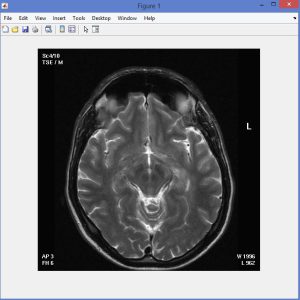

Fuzzy C-Means with Spatial constraint